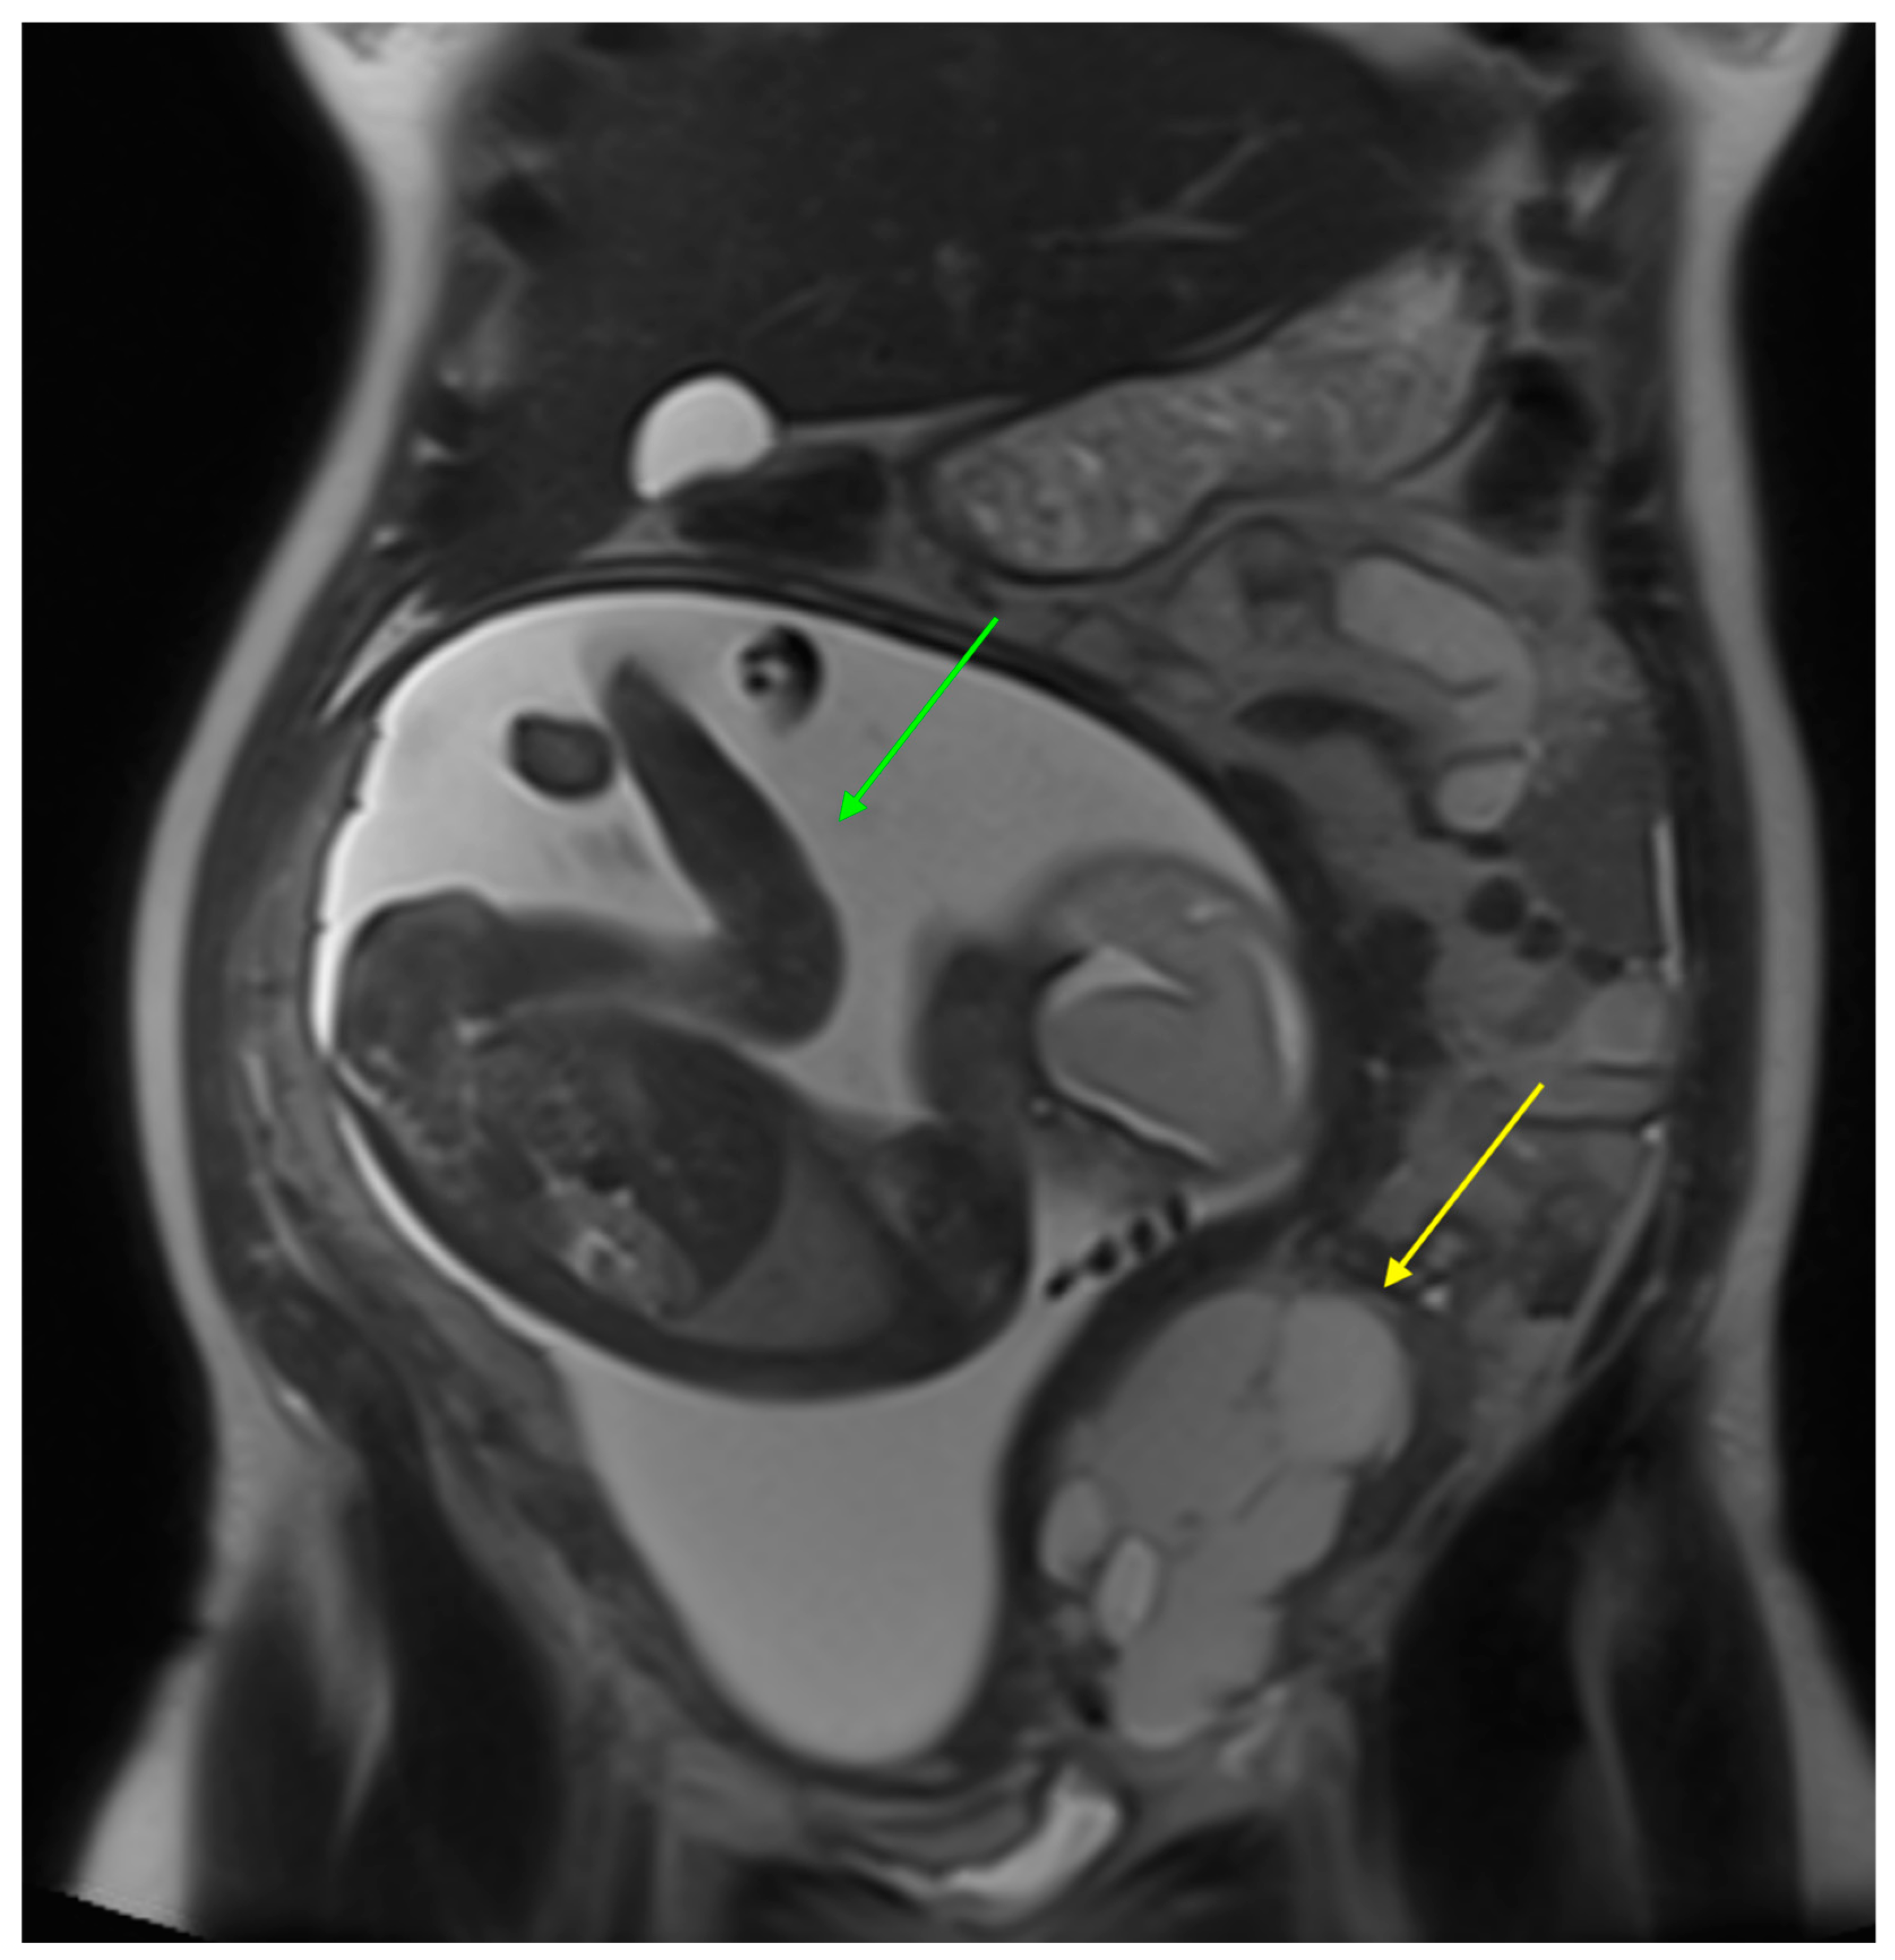

| Vivod | Abdominal pain | 28 | US + MR | 140 | 801 |